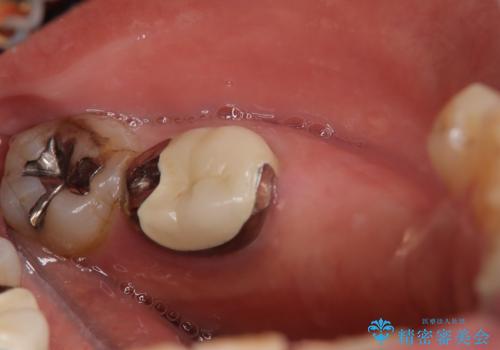

- 定期的に本院に通院されている患者様で、前歯の揺れがあると相談されました。下の奥歯が左右合わせて3本喪失されており、噛み合わせの負担が前歯にも集中していることを説明しました。右下6番の歯に関しては、事前の診査で十分な骨量がありましたのでインプラントを1本埋入しました。左下5番・6番にも本来はインプラントを埋入したかったのですが、骨量が十分でなく、骨を増やす処置をすると神経が近くリスクがあることから、審美性に配慮した金属のばねが見えないノンクラスプデンチャーを製作しました。また、このとき入れ歯を支える左下7番に根尖病変がありましたので、根管治療も行っております。(根管治療は当院院長で専門医を持つDr.林が担当しています。)治療終了後、約1年が経過しましたが、問題なく経過しており患者様も喜ばれていました。